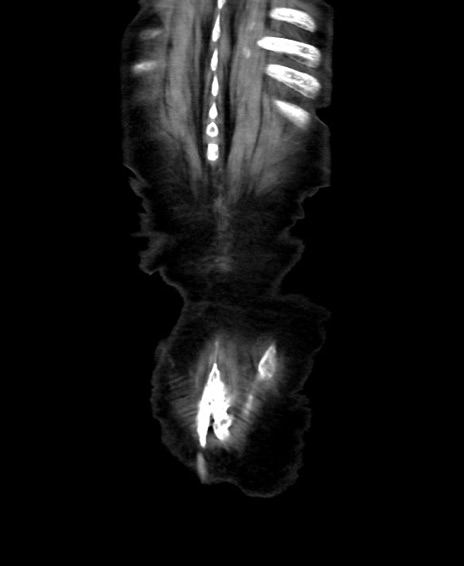

矢状断像